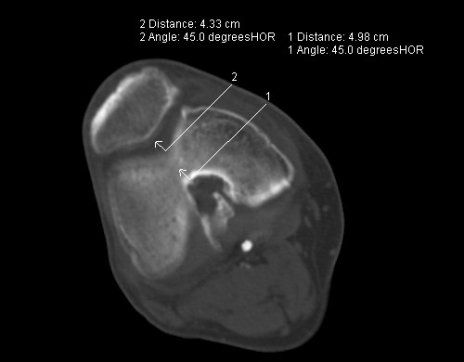

- Coxarthrose, Gonarthrose, Omartrhose sowei Polyarthrose (Gelenkverschleiß)

- 64% der Patienten mit Kniearthrose